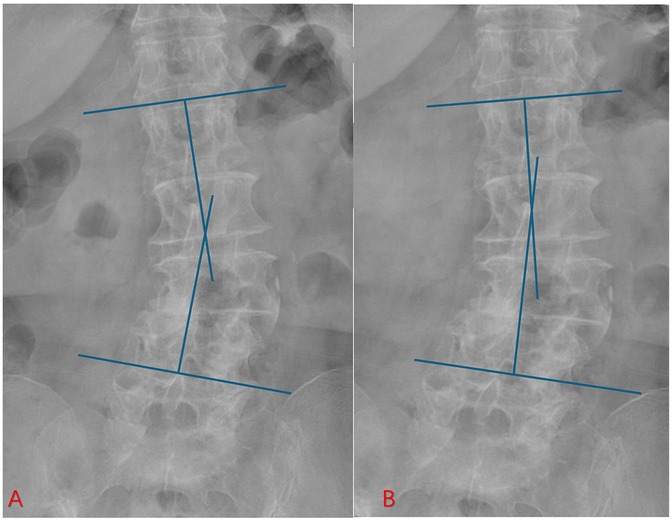

3.5 Typical case

This classic case involves a 71-year-old woman with degenerative lumbar scoliosis (coronal Cobb angle 18°, Figure 3A) who presented with low-back pain and right-leg numbness caused by right-sided L4–L5 lateral recess stenosis. Under general anesthesia she underwent precise decompression via a right interlaminar PEID approach, with an operative time of only 90 min and ∼30 ml blood loss, and no neural or dural complications; she was able to ambulate 6 h post-operatively. Pre-operative MRI (Figure 4A) vs. post-operative MRI (Figure 4B) shows adequate decompression. At 1-year follow-up her leg-and-back VAS had fallen to 1 point and ODI to 20%, while the Cobb angle remained 17° (Figure 3B).

Figure 3. Preoperative and postoperative radiographs of an elderly patient with degenerative scoliosis. (A) Preoperative lumbar x-ray showing coronal deformity with degenerative changes. (B) One-year postoperative follow-up radiograph after PEID. The coronal Cobb angle remained stable without progression of scoliosis, indicating that the PEID effectively relieved symptoms without accelerating deformity progression.